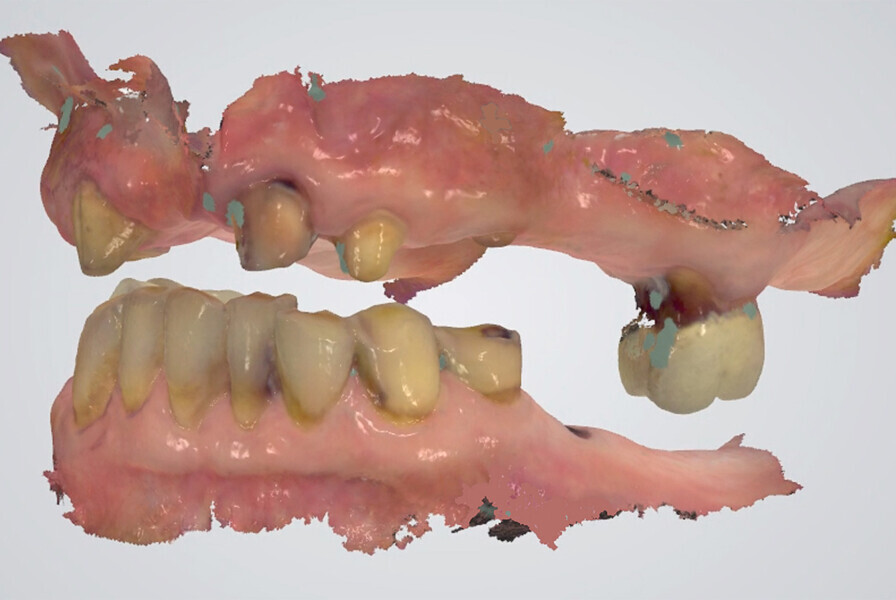

Fig. 25: Digital centric relation recording at the desired vertical

dimension of occlusion of all existing mandibular teeth, in preparation for a fixed complete denture.

Fig. 26: Digital recording of centric relation using a conventional finding method with a composite device at the desired vertical dimension of occlusion.

Fig. 27: Digital recording of centric relation using a conventional finding method with a composite device at the desired vertical dimension of occlusion.